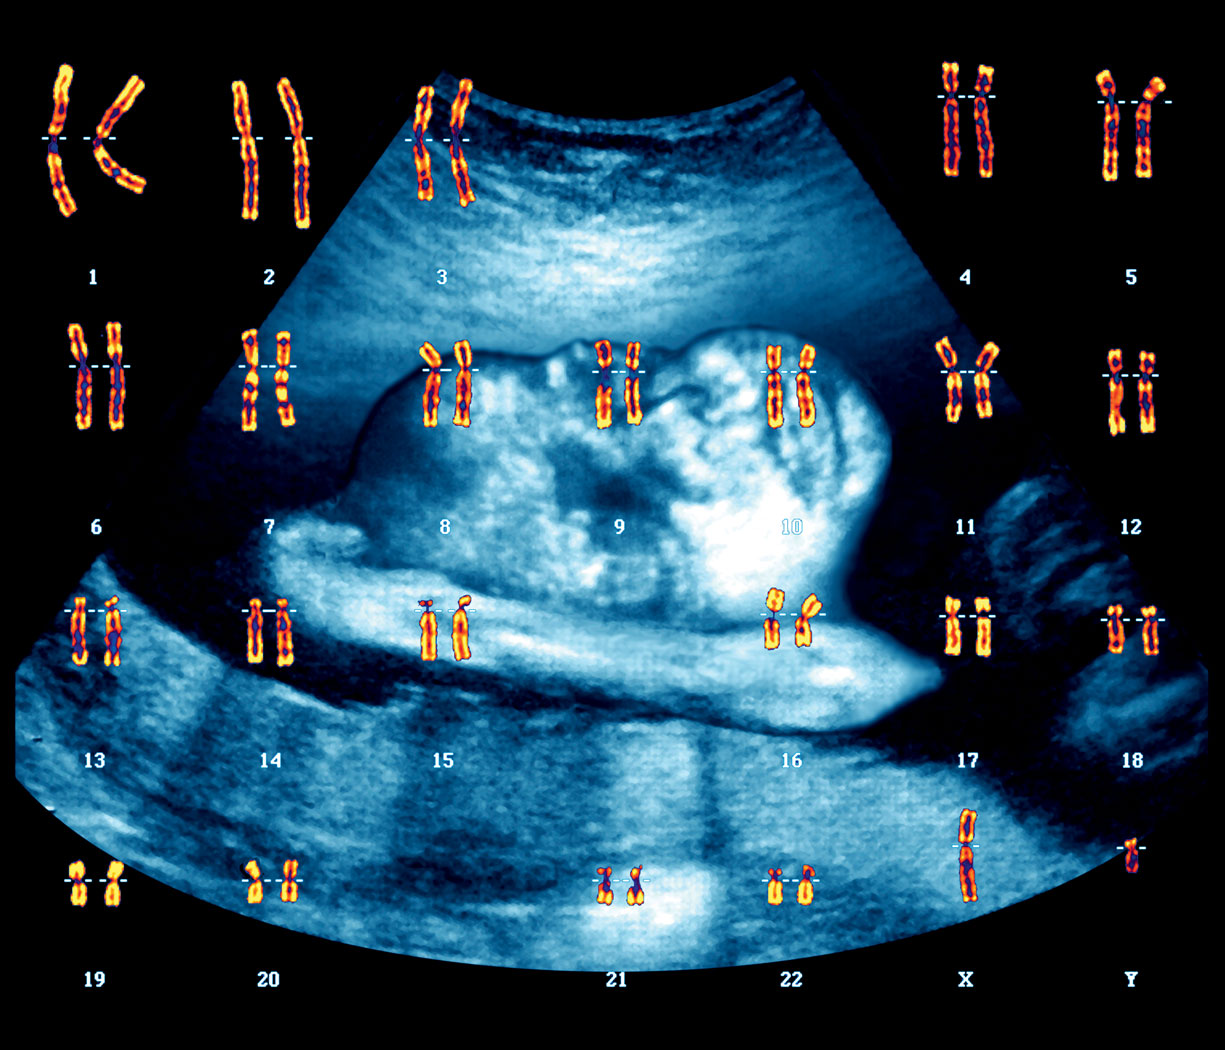

Będzie chłopczyk! Wizualizacja prezentuje pełny zestaw chromosomów, czyli tzw. kariotyp zdrowego mężczyzny (chromosom płci XY). W tle USG płodu. Będzie chłopczyk! Wizualizacja prezentuje pełny zestaw chromosomów, czyli tzw. kariotyp zdrowego mężczyzny (chromosom płci XY). W tle USG płodu. Zephyr/Science Photo Library / East News